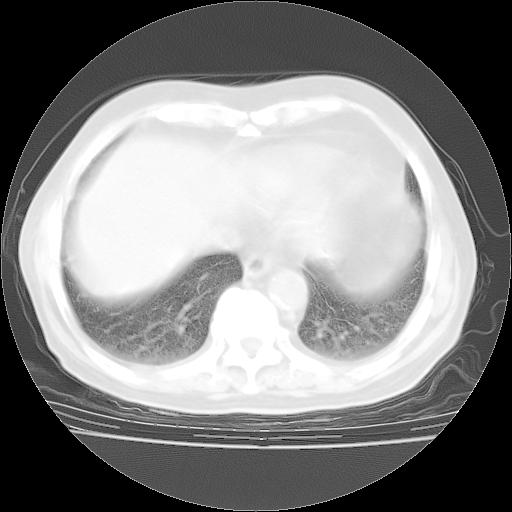

4月28日肺部CT——再次出现类似去年5月9日——透光度降低,“间质性”改变。